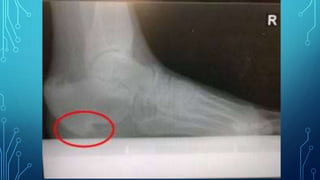

• Imaging Investigation

• A plain lateral X-ray can help to exclude a stress fracture,

and will often show what looks like a bony spur on the

undersurface of the calcaneum.

• 10. • Imaging Investigation • A plain lateral X-ray can help to exclude a stress fracture, and will often show what looks like a bony spur on the undersurface of the calcaneum.